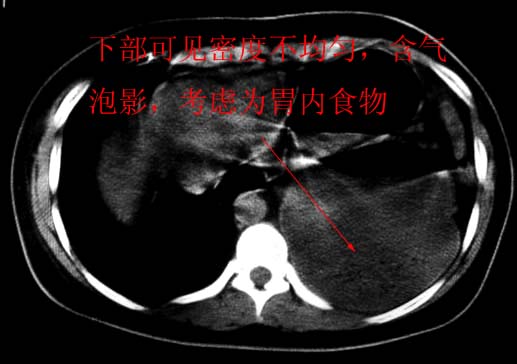

标题: CT5517:女性、24岁,反复胸痛、气促不能平卧半月。 [打印本页]

标题: CT5517:女性、24岁,反复胸痛、气促不能平卧半月。

左肺可见二个含气或液气的囊状影,左肺段支气管、左肺动脉显示不清,纵隔右移,考虑:左肺支气管肺囊肿,左肺发育不良,纵隔疝。

左侧气液腔与胃腔影相连,考虑膈疝。钡餐检查有助于诊断。

我看这是膈疝,在纵隔窗第六\\七幅图像上可见胃粘膜影,再者可见两个腔影,这在液气胸是不会有的.

支持膈疝,纵隔窗内可见消化道的内容物。

“反复胸痛、气促不能平卧半月”。+影像学表现=膈疝